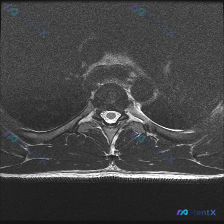

最近遇到一个有意思的病例,临床怀疑胸椎椎间盘病变,但是影像结果却很有意思,整理出来和大家分享一下思路。 病例核心背景 临床核心问题:患者存在胸背部不适/疼痛,临床怀疑为胸椎椎间盘病变,提供单张胸椎MRI T2加权轴位影像要求分析。 --- 影像核心信息 我们先来看这份影像的评估结果: 1. 序列与解...

今天整理了一份有意思的胸椎MRI读片病例,跟大家分享一下,核心问题是初始找椎间盘病变,结果发现了更关键的病变,先把影像资料和分析思路整理给大家。 一、影像基础信息 这份是胸椎MRI矢状位T2加权图像,覆盖T1到T12全胸椎序列,图像质量尚可,无明显伪影,胸椎生理后凸曲度存在。 二、常规评估结果 1....